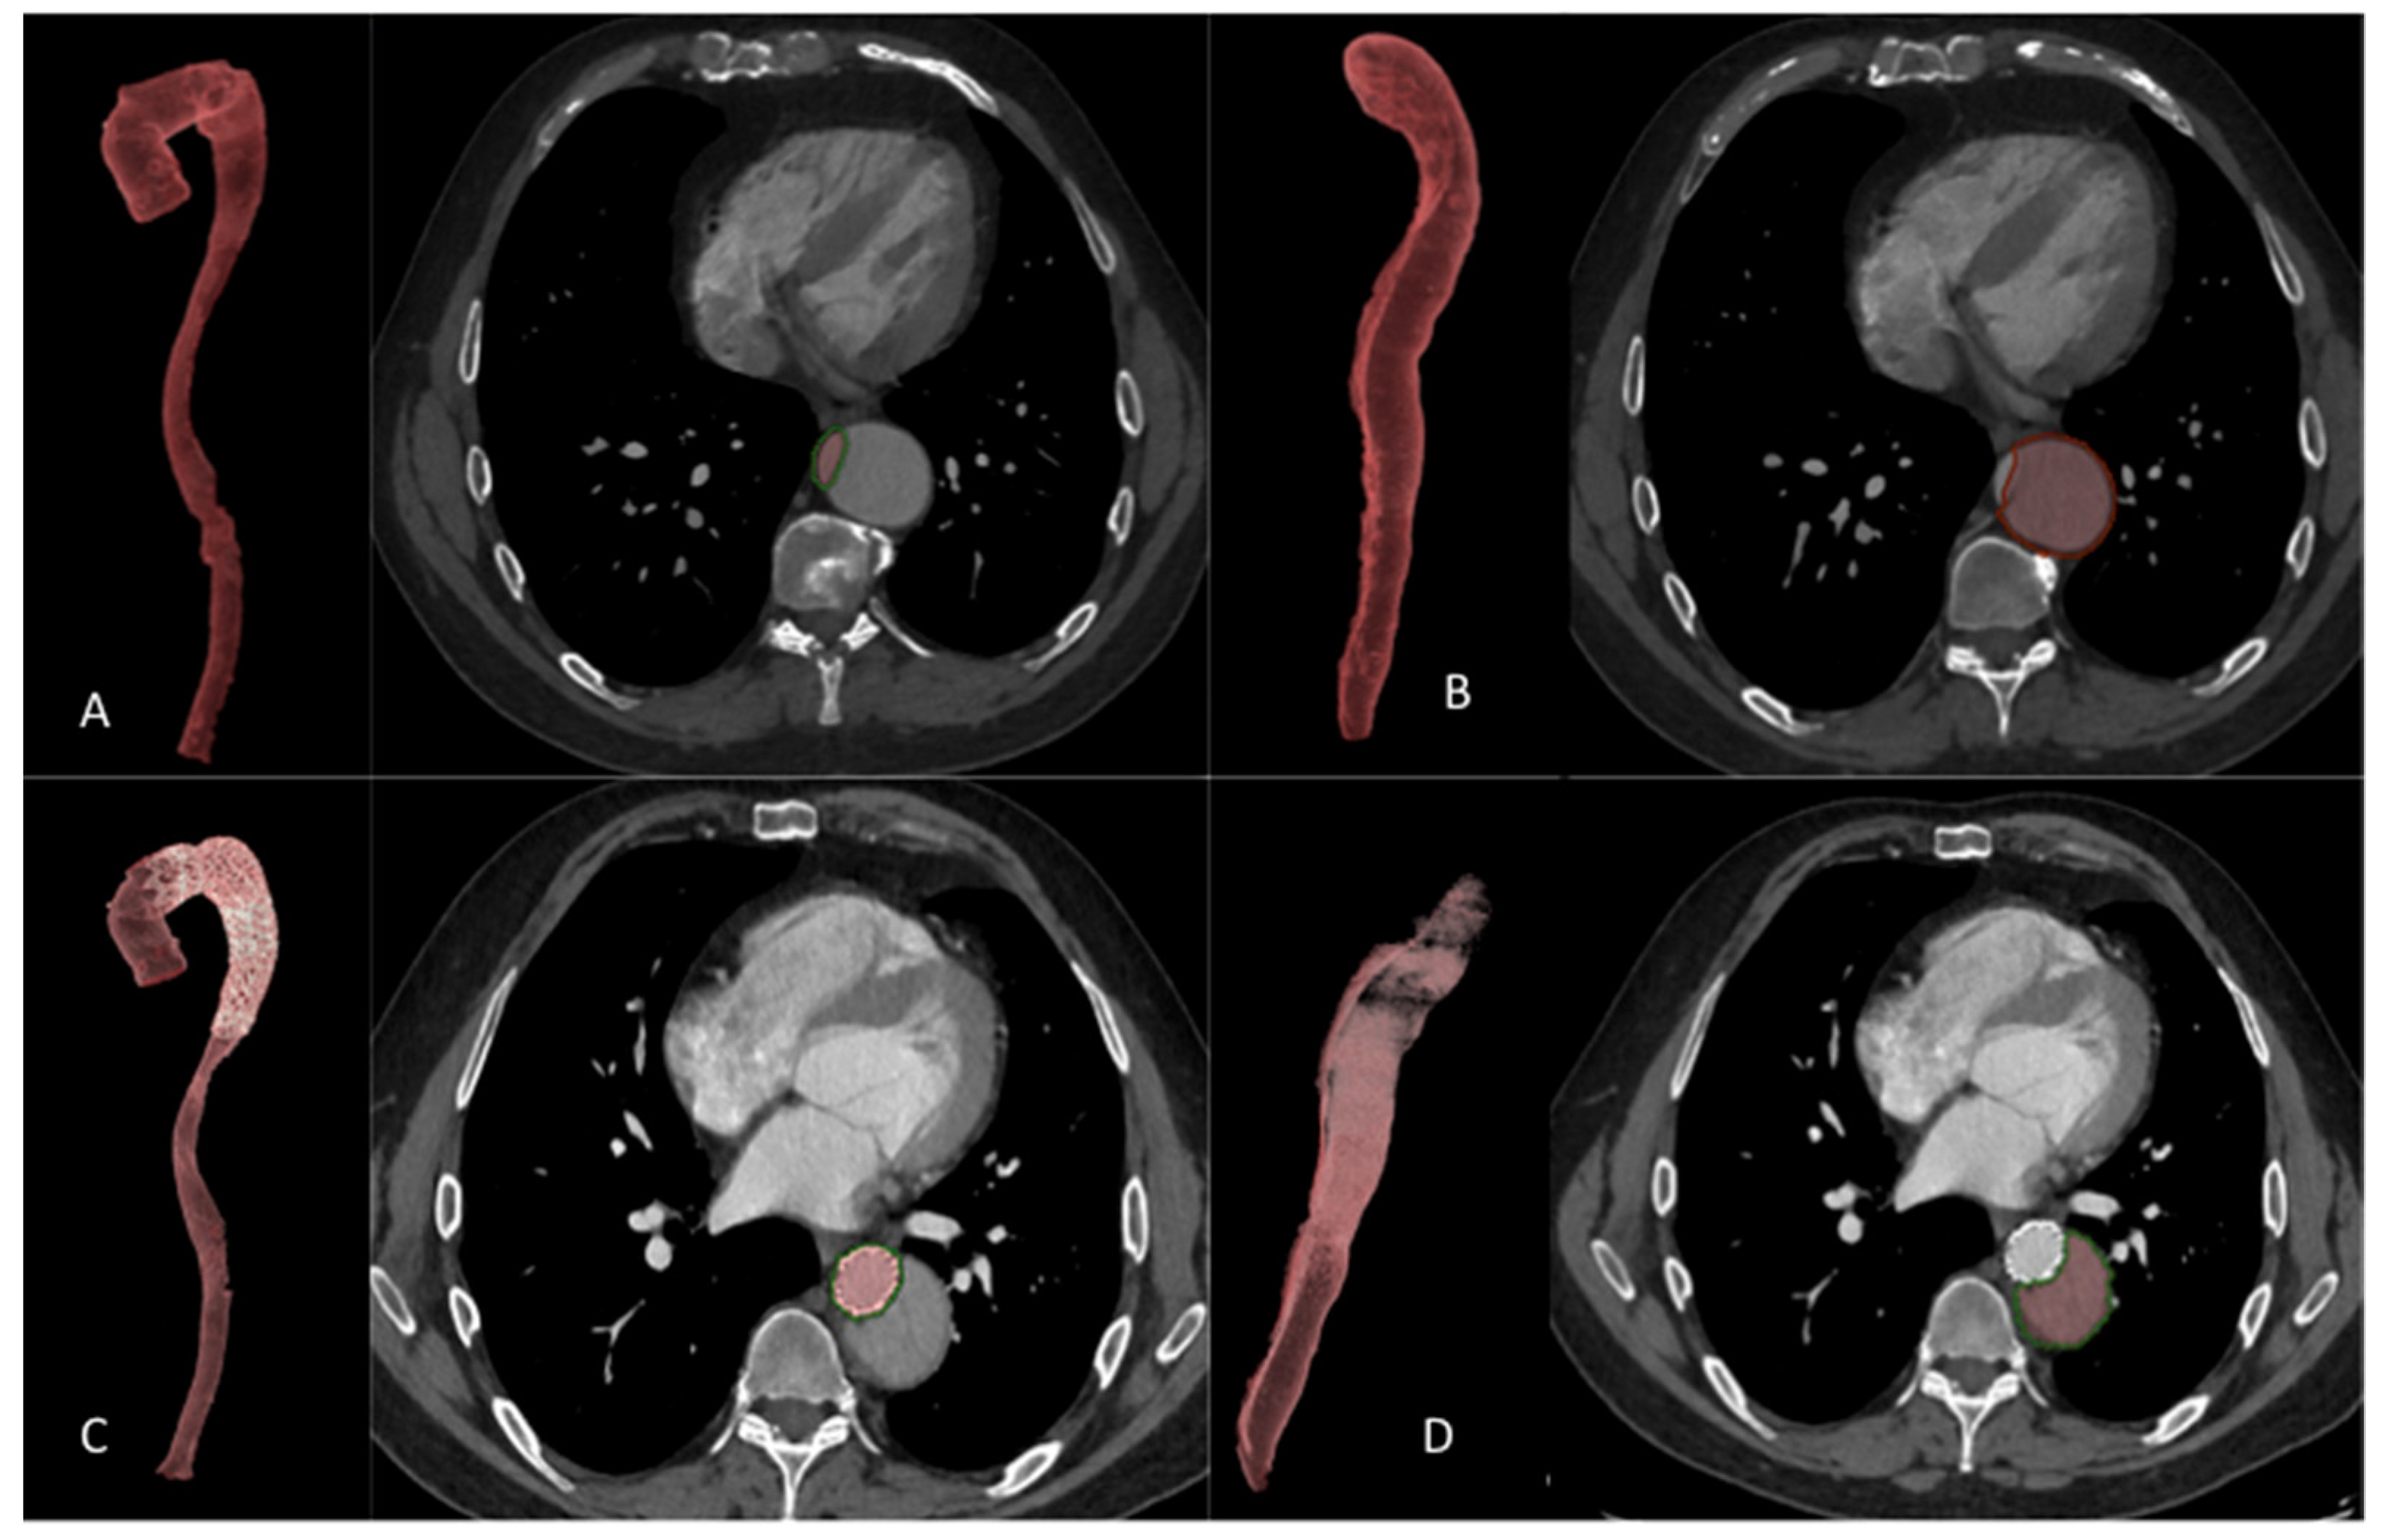

2.8. Volume Analysis

3.3. Anatomical Results

3.3.1. Diameter Analysis

3.3.2. Volume Analysis